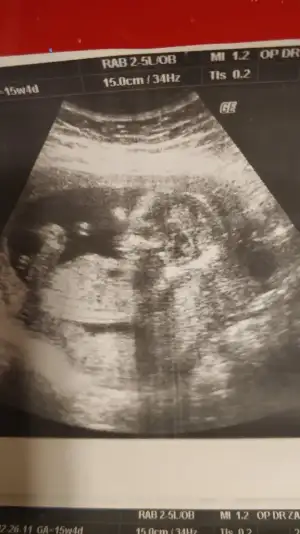

tmm ben ayrıntılı ultrasonda netleşince size dönüş yapacağımBencede kız 2 defa kız demiş aynı drusg de nub da kız gibi geri dönüş yaparsanız sevinirim

M mely15 bi bakarmısın canım ben tahmin ettim arkadaşa sen ne diyorsun 12+4 usgKızlar kızlarvideodan ekran görüntüsü aldığım 2 fotoğrafta nub birinde paralel birinde dik duruyor hareket ettiği sırada değişiyor olabilir mi

bilemedim sizede ekleyim istedim yakaladığım kısımları ❤ M mely15

Ikra meyra Eki Görüntüle 2601535 Eki Görüntüle 2601536

Kız gibiIkra meyra tekrar usg paylaşın demiştiniz sat a göre 12+1 ultrasona göre 12+6 çıktık ❤Pazartesi tekrar gideceğim ama bunu da atmak istedim belki bir tahmin olur